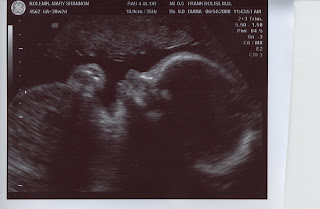

We went for our 30 week sonogram over the weekend and my how Mary Pat has grown! She tipped the scales at exactly 4 pounds. Our technician mentioned that a good rule of thumb is that babies tend to double whatever their weight is at the 32 week mark, which means we could be looking at a robust birthweight in the neighborhood of nine pounds! Mommy will take that epidural with a twist, and don't be afraid to be a little heavy-handed Mr. Anesthesiologist!

Everything seems to be progressing along nicely and normally. The sonogram prints are easier to decipher this time around and there are even some 3-D shots that are both amazing and surreal. Our little ham was playing to the camera and stuck her tongue out at us to say hi in some action that took place off camera. We are getting more excited by the day and hope you enjoy these pictures as much as we do.